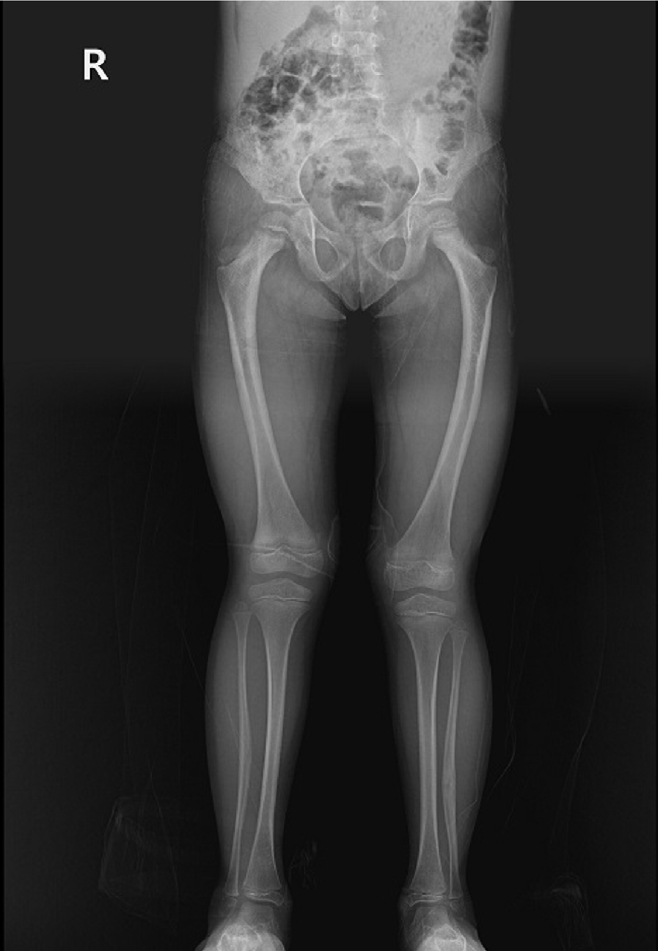

Fig. 6.

Prefracture radiographs of a 73-year-old female patient who subsequently presented with a femoral shaft fracture demonstrating cortical hypertrophy and microfracture. (A) Anteroposterior view. (B) Lateral view.

jmt-2025-00388f6.jpg

A 73-year-old female patient visited our emergency room complaining of pain in the left thigh that had begun approximately a month ago. She had undergone intramedullary nail fixation for a left femoral intertrochanteric fracture 9 years prior and reported no history of recent trauma. The patient had initially sought treatment at another hospital for her left thigh pain and was discharged after conservative management. However, she experienced sudden severe pain accompanied by a breaking sound while walking. Upon examination, her BMD at the L3‒4 levels was noted to be ‒3.1. The patient also had a history of rheumatoid arthritis and hypertension, with no history of cancer. Radiographic evaluations, including anteroposterior and lateral views of the left femur, revealed a left femoral shaft fracture and metal breakage at the distal locking screw fixation site of the previously inserted intramedullary nail. Notably, when the patient first visited the other hospital, a hypertrophy and microfracture were observed at the lateral site of the distal locking screw insertion (Figs. 6, 7). Following the diagnosis, the patient underwent intramedullary fixation using a long nail. Subsequent follow-up evaluations indicated successful bone union at the fracture site.

All three patients had no history of taking bisphosphonates. Hypertrophy of the femur lateral cortex was observed at the fracture site in all three patients. The first patient with synostosis of the hip joint had no range of motion of the right hip joint. As the weight-bearing force was not properly distributed during walking, femur lateral bowing was induced, and tensile force was continuously applied to the lateral cortex of the proximal femur. The second patient had an underlying disease of osteogenesis imperfecta. As a result, the weakened femur showed lateral bowing, and similarly, tensile force acted upon weight-bearing. The other patient underwent intramedullary nail fixation due to a previous femoral intertrochanteric fracture. As the distal locking screw of the intramedullary nail exerted a sustained tensile force on the femur lateral cortex, hypertrophy also occurred around the distal locking screw head.